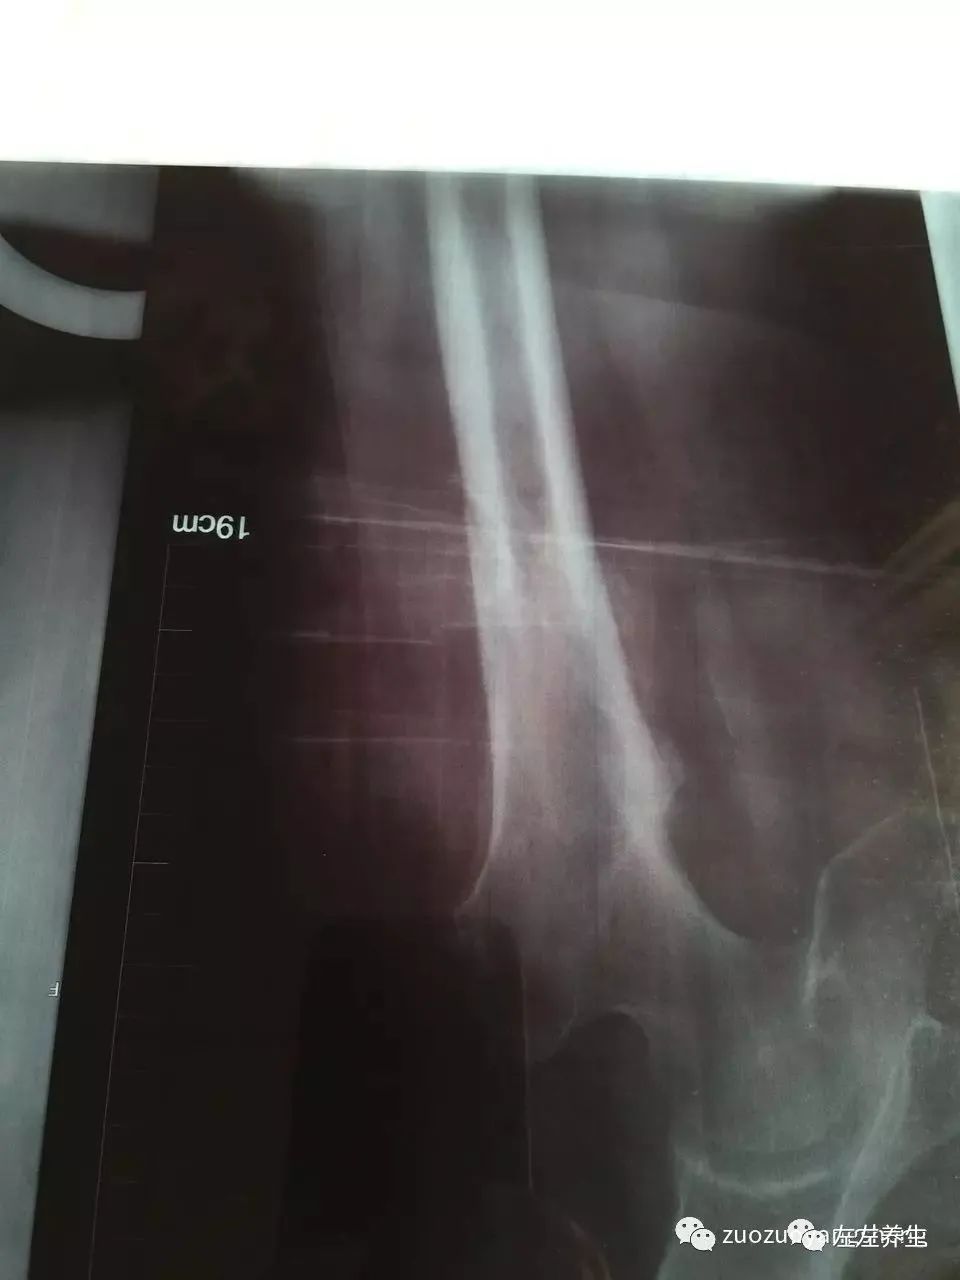

2、牵引四周后(点击可看大图)

牵引期间,在骨折处时敷药酒时敷姜膏、贴暖宝宝、喝姜汤,后改为喝参粉汤(1天4次)。医生说牵引需要8到12周,但我母亲在牵引4周时就已长出一些骨架,考虑到年龄因素继续牵引至6周,拍片显示骨头愈合非常良好,开始慢慢撤牵引,医生建议再继续在医院多观察两周,然后就可以回家安养。在这治疗过程当中,运用原始点的方法帮着内外调理,取得了显著的效果,被医生称之为奇迹,并成为医院的案例,可以作为以后同样患者治疗的一个指导。